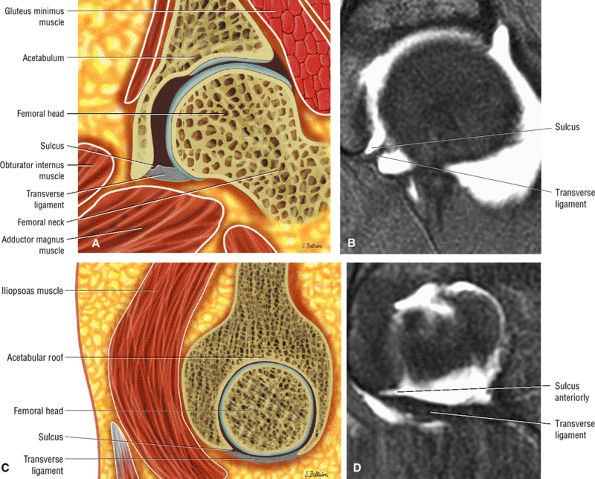

The stellate lesion or crease represents a normal bare area superior to the acetabular fossa.

The transverse acetabular ligament bridges the incomplete acetabular ring inferiorly. The acetabular labrum ends at the anterior and posterior margins of the inferior aspect of the acetabulum.

Normal labral variants are visualized posteroinferiorly, anterosuperiorly at the junction of the transverse ligament and labrum, and between the capsule and labrum lateral to the acetabular rim.

The posterior inferior sublabral sulcus (Fig. 3.60) should not be misinterpreted as a posterior labral tear on axial images.15,16 When depicted, this sublabral groove is seen on one or two axial oblique images superior to the transition between the transverse ligament and the posteroinferior labrum. This sulcus is in fact characterized as a labrocartilaginous cleft and can be shown arthroscopically.

An anterosuperior cleft (Fig. 3.61) may be seen as a normal variant in the presence of a normal lateral acetabular labrum. On anterior coronal or sagittal images, this cleft is seen as a partial undercutting of the labrum on a single image. The extension of fluid into this cleft occurs from the femoral side. It may be more commonly seen in labral hypertrophy associated with mild developmental dysplasia of the hip (DDH).

A transverse ligament-labral junction sulcus is a normal sulcus or recess that may be seen between the transverse ligament and the labrum either anteriorly (Fig. 3.62) or posteriorly (Fig. 3.63). The perilabral sulcus (Fig. 3.64) represents a normal space between the acetabular labrum and capsule visualized on coronal images. The capsule attaches directly to the osseous rim of the acetabulum. A normal sulcus may exist at the junction of the transverse ligament and labrum (see Fig. 3.62) on medial sagittal images. A normal perilabral sulcus is present on coronal images between the capsules and labrum and does not represent a pathologic detachment. This sulcus is a distinct and normal potential separation from the labrum (Fig. 3.65). The

FIGURE 3.54 ● Transverse ligament. (A) Arthroscopic view. (B) Coronal T2* gradient echo image. (C) Sagittal FS PD FSE medially. (D) Sagittal FS PD FSE at posterior labrum-transverse ligament transition.